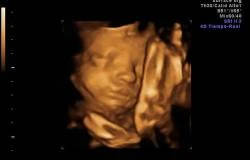

Un equipo de investigadores de las universidades de Durham y Lancaster (Reino Unido) sugiere que los fetos bostezan dentro del útero, un proceso de desarrollo que podría dar a los médicos otro índice de salud.

Mientras algunos expertos han sugerido que los fetos bostezan y otros afirman que es simplemente la apertura bucal, este estudio distingue claramente el bostezo, del no bostezo o la boca abierta, centrándose en la duración de la apertura de la boca.

Los investigadores analizaron las secuencias de vídeo 4D de 15 fetos sanos (ocho femeninos y siete masculinos) de entre 24 a 36 semanas de gestación para examinar de cerca todos los acontecimientos en un tramo de aftosa en el feto y hallaron que más de la mitad de las aberturas de la boca observadas fueron bostezos, según publica este miércoles la revista 'Plos One'.